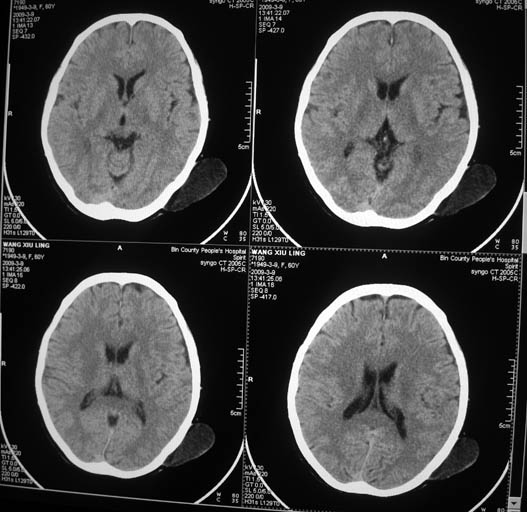

标题: CT18574:女,60岁,头部肿物。 [打印本页]

标题: CT18574:女,60岁,头部肿物。

女,60岁,头部肿物。ct值为12hu。

考虑-----皮脂腺瘤或皮样囊肿可能性大

至此考虑皮样囊肿

考虑皮脂腺瘤或皮样囊肿。